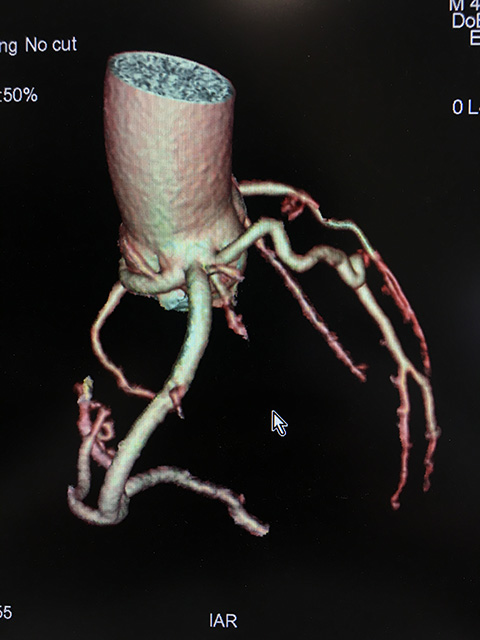

让患者稍作休息后,3月12日,评估患者病情后,李主任再次带领团队为黄先生行冠脉造影,查看冠脉情况,术中冠脉未见明显狭窄,但有意思的是,李主任发现回旋支开口于右窦,与右冠状动脉共开口,向左室前壁绕行,分布于左室侧壁。也就是说,黄先生的心脏血管存在畸形。李主任术中对团队成员说:“这种畸形并不常见,此种畸形应是先天性的,患者现已40岁,血管目前无明显狭窄,血管是可以满足心脏供血的,暂无需特殊处理。”接着李主任再行左室造影,提示左室符合心尖部心肌肥厚图像。至此,黄先生突发心跳骤停,很可能就是心肌肥厚引起的。为了能够更好的查看患者的心肌情况和重建心脏血管,李主任为黄先生进一步进行了心脏核磁共振和冠脉CTA检查,检查提示黄先生的确患有心肌肥厚,黄先生的心跳骤停也很可能是因为心肌肥厚诱发室颤导致的。